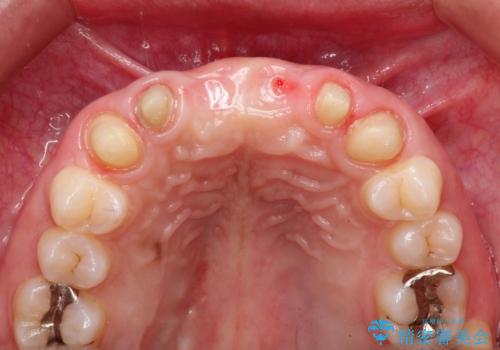

- 数ヶ月前に治療終了したブリッジの歯ぐきの違和感が強く、改善を求めて来院されました。

歯ぐきは著しく腫れ、少し触ると出血してしまうような状態であったためブリッジの再作製・歯周外科を用いた歯肉環境の改善を計画します。

- 74万円(仮歯×6・ファイバーコア×4・ジルコニアクラウン×6)費用は治療当時の料金となります